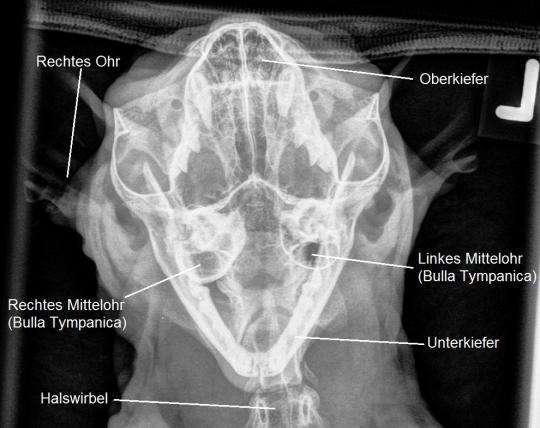

Zur Diagnosesicherung wird in Sedation ein Schädelröntgen angefertigt - hier ist ersichtlich, dass die filigrane Knochenstruktur des rechten Mittelohres ("Bulla Tympanica") stark verdickt ist - ein Hinweis auf die chronische Entzündung, welche durch den im Mittelohr und Gehörgang wachsenden Polypen verursacht wird.

Im Falle von Murphy wurde eine nachhaltigere, aber auch invasivere Therapiemethode angewendet. Insbesondere da sich die Paukenhöhle (Mittelohr) der Katze im Röntgen stark verändert präsentierte, was auf eine starke Verankerung des Polypen im Mittelohr hinweist, wäre ein reines "Ausreissen" des Gewächses kaum erfolgreich gewesen. Der Umstand, dass zusätzlich eine partielle Entfernung des Gehörganges nötig wurde, unterstreicht diese Einschätzung.